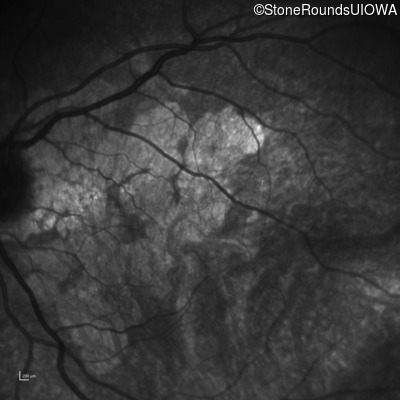

Highlighted Images

Age at visit: 55 years

OD OS